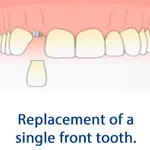

Replacing teeth with Dental Implants is a better treatment than many other traditional methods. The implants are screw like structure which are placed within the jaw bone. The implants act like the roots of teeth and provide support to the crown (missing teeth). The results with dental implants look, feel and function like natural teeth.

The biggest advantage of dental implant over a conventional bridge is that the implant crown emerges outside the gum and is independently supported without the help of the adjacent teeth.

A traditional method of replacing the missing tooth is through Bridge where the artificial tooth is supported by adjacent teeth. Dental Implant is better than Bridge because there is no need to cut the natural teeth as is done for a bridge.